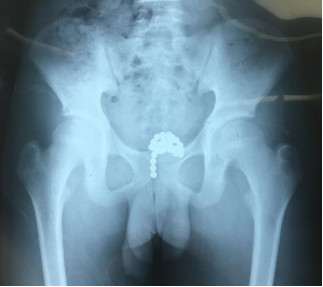

一个孩子误吞了一串磁力珠,这种珠子磁力很大,会快速的压破肠管,从而引起肠穿孔,并且不是一个部位穿孔,是多部位穿孔。幸亏抢救及时,这个孩子没有生命危险,否则后果真是难以想象。

不仅仅是消化道,还有把磁力球塞进尿道膀胱的。想想都“佩服”孩子的“勇气”。